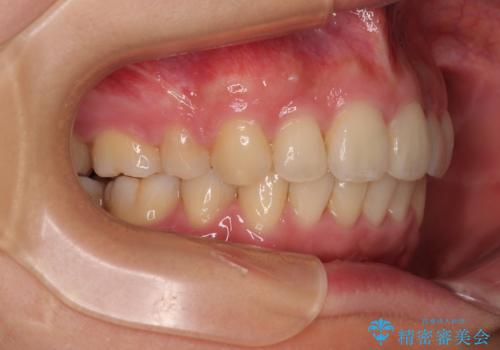

全顎的なデコボコと口元の突出感 ワイヤー装置での抜歯矯正で整った口元に

- 奥歯も含めて全体的なデコボコと前歯の突出感を気にして来院された患者様です。

上下左右第一小臼歯4本を抜歯し、ワイヤー装置にて矯正治療を行うこととしました。

前歯の突出感がなくなり、仕上がりには大変満足していただけました。